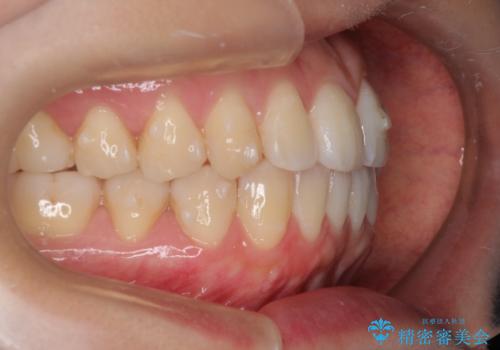

初診時の歯並びの状態としては、上下ともに前歯部に限局した軽度ののがたつき(叢生)がある状態でした。

主に歯列弓の拡大とディスキング(歯と歯の間に隙間を作る処置)を行い叢生を改善しました。

見た目、嚙み合わせ及び、治療期間や施術内容に大変ご満足いただきました。